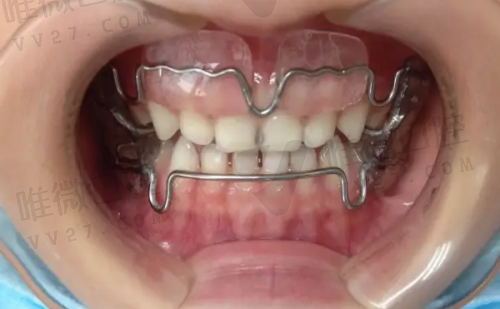

◎ 金属自锁矫正:7000元+起

◎ 时代天使隐形矫正:13000元+

◎ 隐适美进口矫正:约19000元起